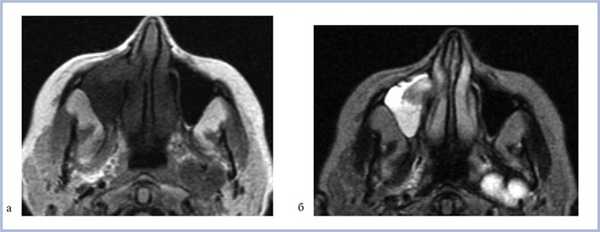

При МРТ-исследовании у 8 (80%) больных определялось асимметричное снижение интенсивности сигнала в режиме Т1 от ретромаксиллярной клетчатки, а ее истончение выявилось в 3 (30%) случаях. Изменений со стороны костной стенки у этих больных не выявлено.

При МРТ жировая ретроантральная клетчатка имеет высокие значения интенсивности сигнала в режимах Т1 и Т2. При локальном отеке клетчатки интенсивность сигнала меняется [12].

Больная Б., 43 года, проходила исследование в отделении компьютерной томографии КОКБ по поводу объемного образования среднего уха. В качестве случайной находки выявлена правосторонняя одонтогенная киста (рис. 6, а, б; 7).

Рис. 6. Магнитно-резонансная томограмма верхнечелюстных пазух, изображения в режимах Т1 (а) и Т2 (б), аксиальная проекция.

Рис. 7. Контрольная рентгеновская компьютерная томограмма в аксиальной проекции, мягкотканный режим.